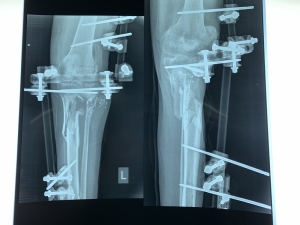

A raíz de las protestas de la Gran Marcha del Retorno en Franja de Gaza, nuestros equipos en el enclave palestino se enfrentan a la ardua labor de reemplazar los centímetros de huesos que han sido pulverizados por las balas israelíes en los cuerpos de los manifestantes.

Cada nuevo casos constituye un reto y ningún herido puede compararse

Entrevista al doctor Ali Al-Ani, médico ortopeda en el proyecto de cirugía reconstructiva de MSF en Ammán, Jordania.